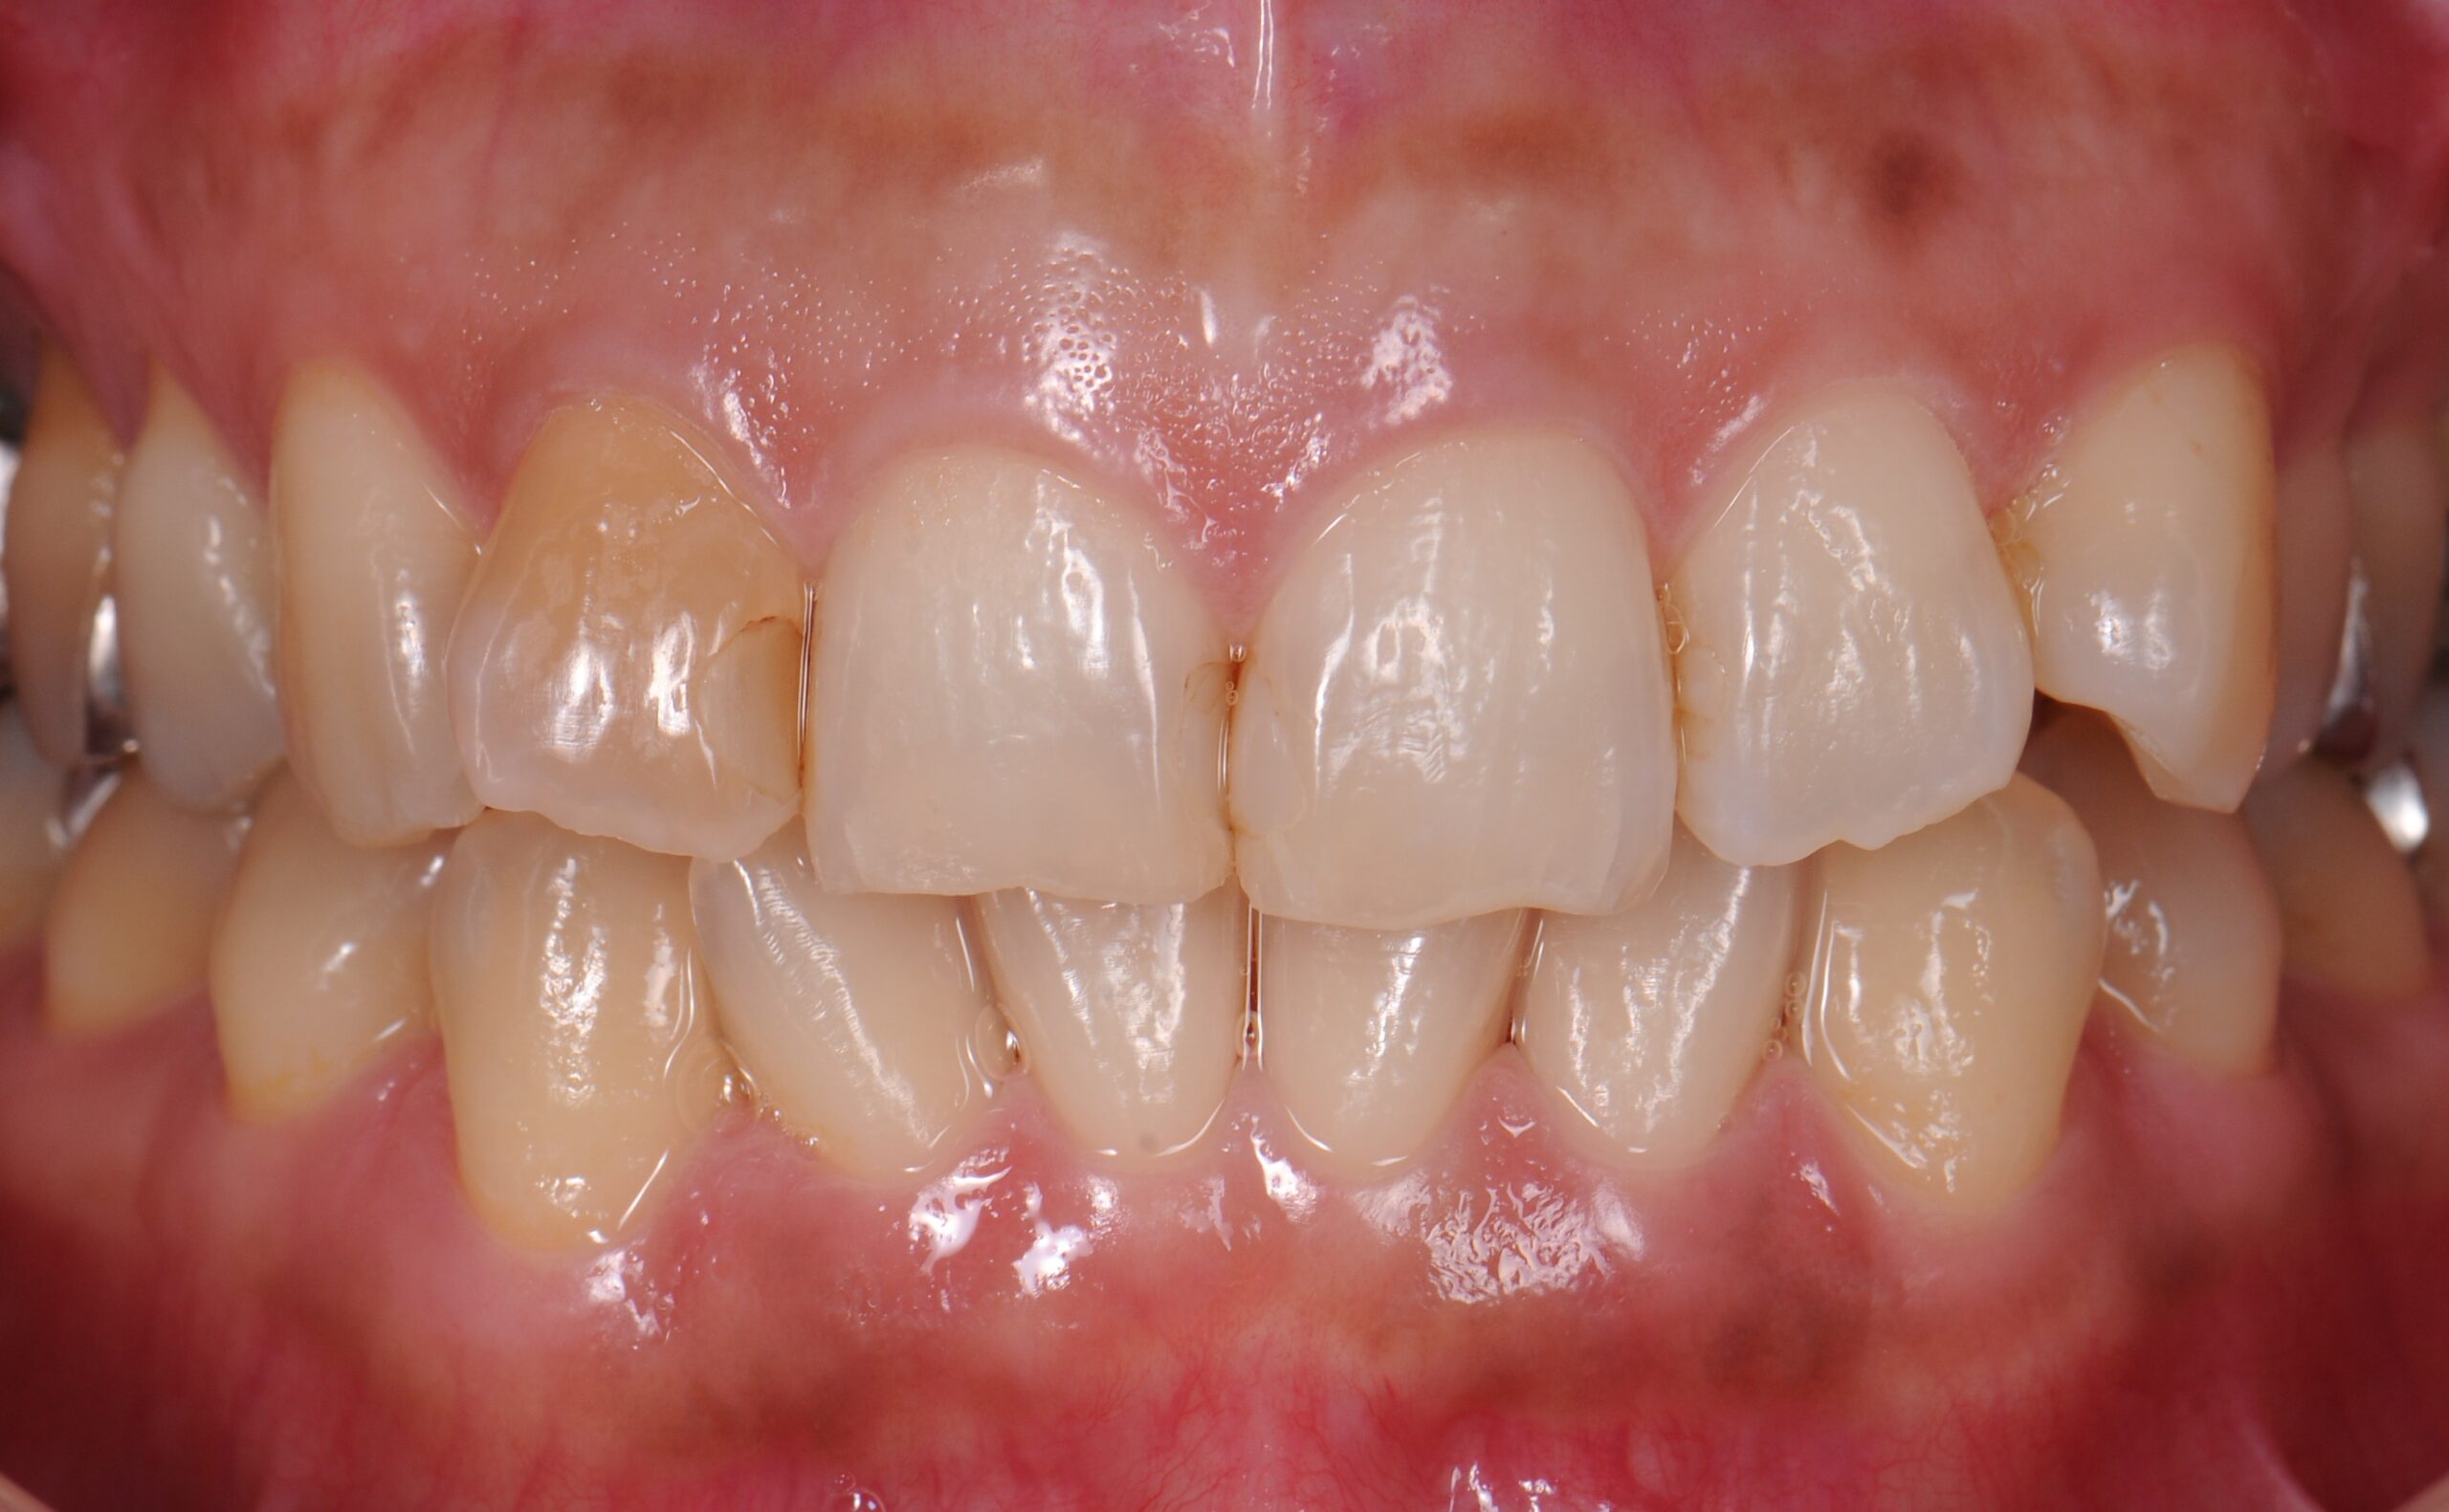

case2 症例(セラミッククラウン前歯)

治療後

| 費用(税込み) | 154,000円 |

| メリット・デメリット | デメリット 歯質を削合する必要がある |

| 治療回数 | 4-6回(根管治療は別) |

| 主訴 | 変色が気になる |